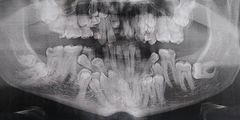

사랑니 엑스레이 올타임 레전드